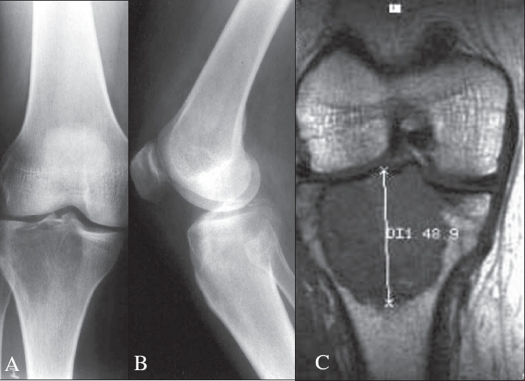

- Imagen clave: Lesión lítica excéntrica, metafisoepifisaria, sin matriz calcificada, que adelgaza y expande la cortical. Límites bien definidos pero sin esclerosis periférica. RM: extensión a partes blandas y relación con la articulación.

3.1 Radiografía simple

- Localización: Lesión lítica, excéntrica, metafisoepifisaria (afecta la epífisis y se extiende a metáfisis).

- Límites: Bien definidos, pero sin esclerosis periférica (a diferencia del fibroma no osificante). Zona de transición estrecha.

- Cortical: Adelgazamiento y expansión, con posible rotura y extensión a partes blandas.

- Matriz: No hay mineralización (ausencia de calcificaciones).

- Espacio articular: Puede estar respetado o invadido en casos avanzados.

3.2 Resonancia magnética (RM) - Técnica de elección

- Extensión intraósea: Determina la afectación real de la médula.

- Extensión a partes blandas: Evalúa la masa extraósea.

- Relación con la articulación: Evalúa la integridad del cartílago articular y la posible invasión subcondral.

- Señal: Típicamente hipointenso en T1, hiperintenso heterogéneo en T2. Las áreas de hemorragia o quísticas pueden dar señal variable.